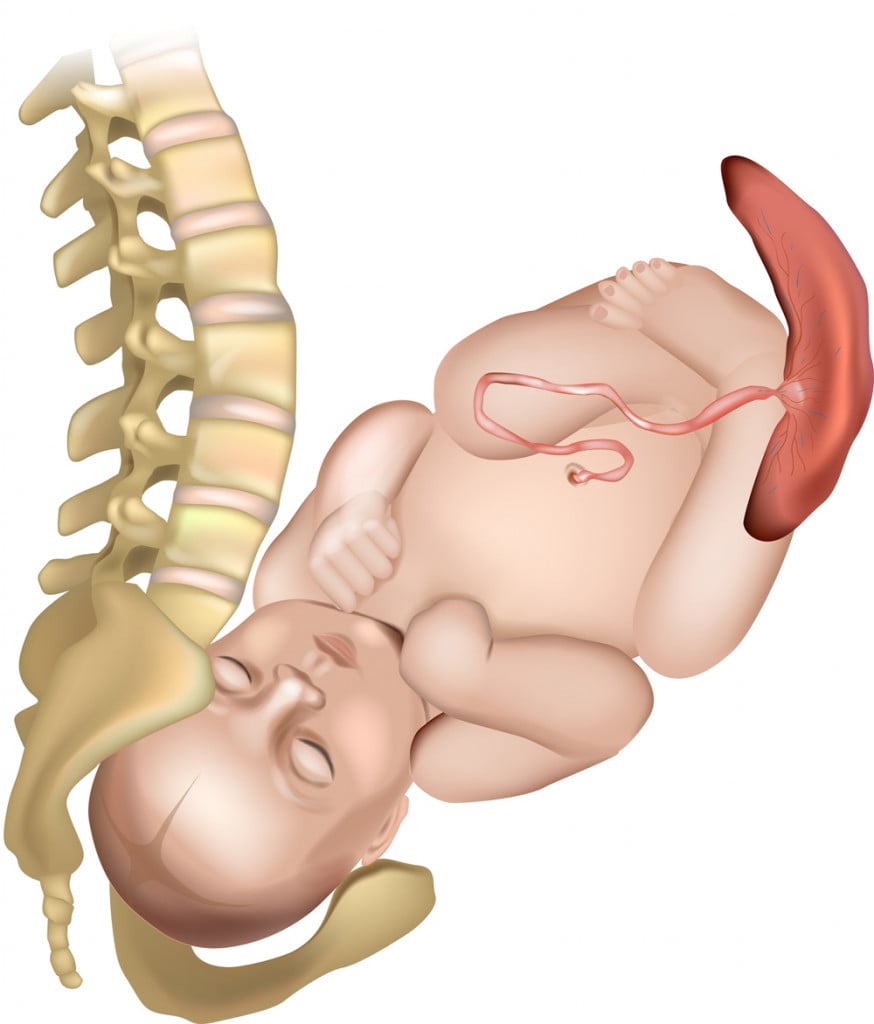

Every single one of these ~200 days are crucial. Development in the womb is incredibly rapid; a single cell absorbs nutrients from the fluid inside the womb, slowly adding components, developing the heart, lungs, skin, hair, and meters of intestines. From chains of chemical molecules alone, bodies can create miniature versions of themselves, with all that they need to become a human adult.

Fetal development is divided roughly into three phases: the germinal, the embryonic, and the fetal stages.

The germinal phase is the shortest, lasting only two weeks. The clump of cells that is the fertilized ovum travels down into the uterus and implants itself into the lining, triggering a host of chemical changes in the parent. The cells, which are like a blank page, start differentiating—one into a future heart cell, another into a future neuron, a third to make up your bones, and so on.

The embryonic stage starts in the third week and lasts until the eighth. The nervous system forms the spinal cord during this time.

Almost every organ and limb develops into its final form during the fetal stage. New nerves and blood vessels form every day, while the digestive and respiratory systems develop in their entirety.

Most anthropologists and biologists believe that babies don’t develop into fully physically and mentally independent beings due to the width of the pelvis. During birth, the baby should rotate downwards, so that the head faces the birth canal. The journey out into the world is a tight fit, with the head just able to make it through.